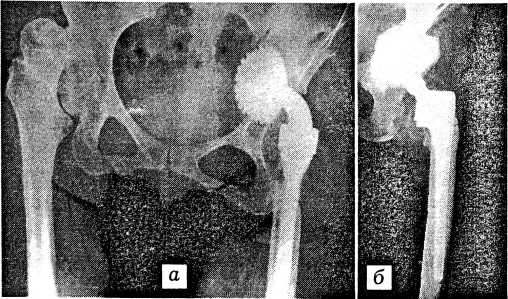

Материал и методы. С апреля 1990 г. по октябрь 1998 г. в отделении эндопротезирования крупных суставов ЦИТО тотальное эндопротезирование тазобедренного сустава выполнено у 1668 пациентов в возрасте от 17 до 80 лет (средний возраст 41,9 года). У 146 больных применен протез Герчева. Более современные металлополимерные разъемные эндопротезы с напылением титановыми шариками, титановой проволокой и другими видами структурирования поверхности имплантированы 1158 пациентам (см. таблицу). У 256 больных установлены эндопротезы «Biomet» (рис. 1), у 337 — «Компомед», у 565 — более совершенные отечественные протезы ЭСИ с использованием вкладыша из хирулена. В 78 случаях применены бесцементные тотальные эндопротезы зарубежных фирм: «Zimmer», «Osteonics», «Intermedics-Orthopaedics», «Endoprothetik Plus» и др.

Рис. 1. Рентгенограммы больной Т. с ревматоидным поражением тазобедренных суставов.

а — до операции; б — после тотального эндопротезирования левого тазобедренного сустава протезом «Віоmet».